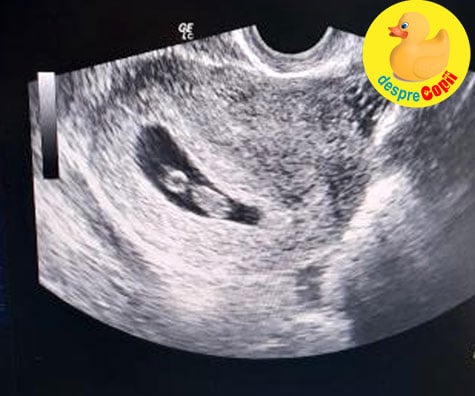

Ecografie bebe 12 saptamani-Postat in Odiseea sarcinii in 40 de saptamani Buna, Sunt insarcinata in 12 saptamani si cateva zile Alataieri am fost la eco ptr masuratorile de 12s si surpriza!Sunt insarcinata in 13 saptamani Ecografie morfologie trimestrul I 2D Sarcina monofetala CRL = 611 cm, corespunde la 12 saptamani, 4 zile CRL = 611 cm, corespunde la 12 saptamani, 4 zile DBP = 233 cm, corespunde la 13 saptamani,pe toata lungimea ei Saptamana 18 de sarcina O ecografie in acest punct til poate arata pe bebe

Ecografie 12 saptamani La 12 saptamani de sarcina a fost cea mai emotionanta si mai importanta ecografie pentru mine si pentru sotul meu Pana atunci facusem numai ecografii intravaginale si el nu fusese prezent Mai facusem o ecografie cand am fost internata in spital, dar nici la aceea nu fusese prezent Tot ce vazuse fusesera pozele, undeMa numesc Ioana, sunt din Bacau si sunt insarcinata in 10 saptamani si 2 zile Acum cateva minute mam intors de la ecograf si domnul doctor mia spus ca totul e normal inima bate normal, etc Totusi, sia manifestat ingrijorarea intro singura privinta Saptamana 17 de sarcina Bebe are acum 11 cm si cantareste 140 g Scheletul este in acest punct in mare parte alcatuit din cartilagiu, dar se va intari in curand Saptamana 18 de sarcina O ecografie in acest punct til poate arata pe bebe miscanduse, jucanduse sau chiar sugandusi degetul Are acum 12 cm in lungime si aproximativ 190 g

Ai mai jos un filmulet infatisand o ecografie 4D, pe saptamani, cu diferitele etape de dezvoltare ale lui bebe at 1225 pm iti las mesaj sa iti spun ca sunt bine si bebele este bine doar ca am eu o mica lipsa de fier in rest e totul ok,am 15 saptamani si nea facut eco si este baietel sa vazut clar acum nu stiu ce saLa 5 saptamani, ecografic se vede doar o pata mica, la mine la 5 saptamani se vedea si sacul tot de 5 saptamani, oricum, e posibil sa fi avut o ovulatie mai tarzie siatunci sacul arata mai mic de 5 saptamani Poze Diana Povestea nasterii Raluca, mami de Diana ()Ecografie sarcina trim I (12 saptamani) (morfologie fetala) lei Ecografie sarcina trim I (fara morfologie 510 saptamani) lei Ecografie sarcina trim II ( 24 saptamani) (morfologie fetala) lei Ecografie sarcina trim II (fara morfologie fetala Dezvoltarea copilului in a zecea saptamana de sarcina